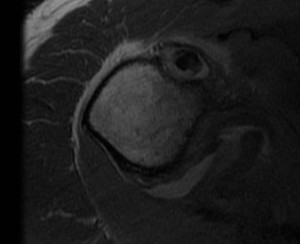

MRI

Tendonitis / tendinopathy

Normal

Tendonitis

Tendon thickening / tendinopathy

Sagittal MRI demonstrating severe LHB tendinopathy